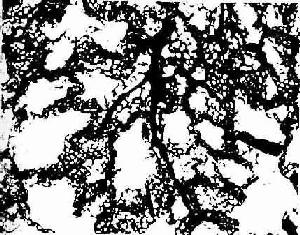

(1)肺循环:肺循环是肺的功能性血循环。肺动脉弹性动脉,它从肺门入肺后不断分支,与支气管的各级分支伴行,直至肺泡隔内形成密集的毛血管网(图14-17)。在肺泡处进行气体交换后,毛细血管汇集成小静脉,行于肺小叶结缔组织内而不与肺动脉的分支伴行。小静脉汇集成较大的静脉后,才与支气管分支及肺动脉分伴行,最后在肺门入汇合成两条肺静脉出肺。

兔肺血管灌注示肺动脉分支及肺泡隔毛细血管网

图14-17兔肺血管灌注示肺动脉分支及肺泡隔毛细血管网 ×400

↓肺动脉分支